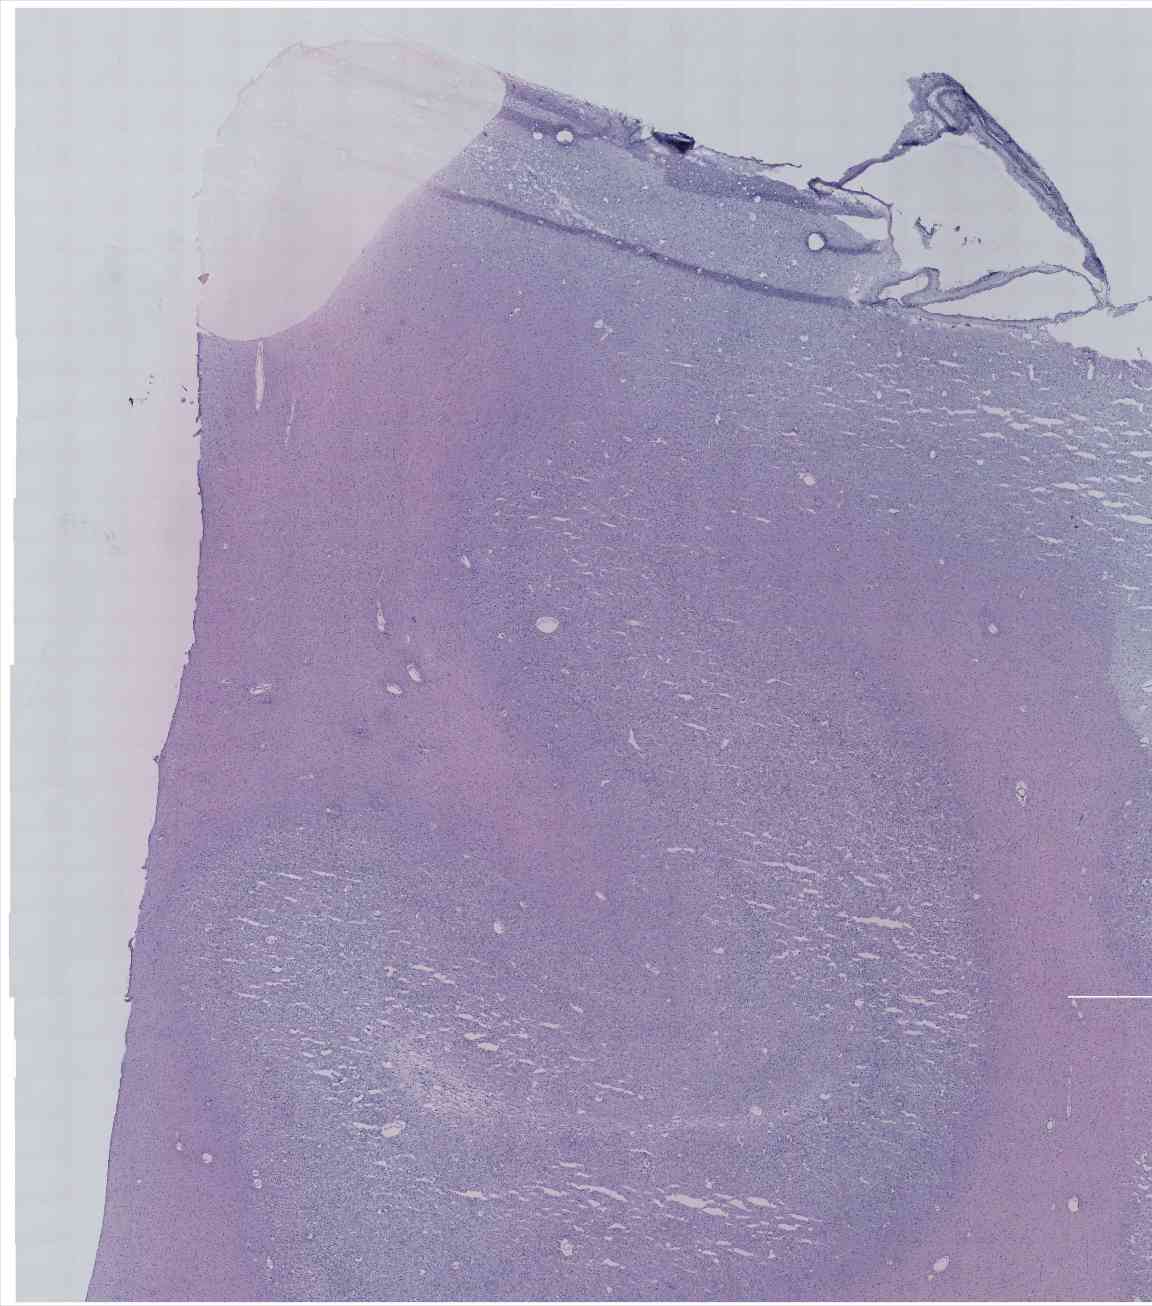

Chip 049 Well C1